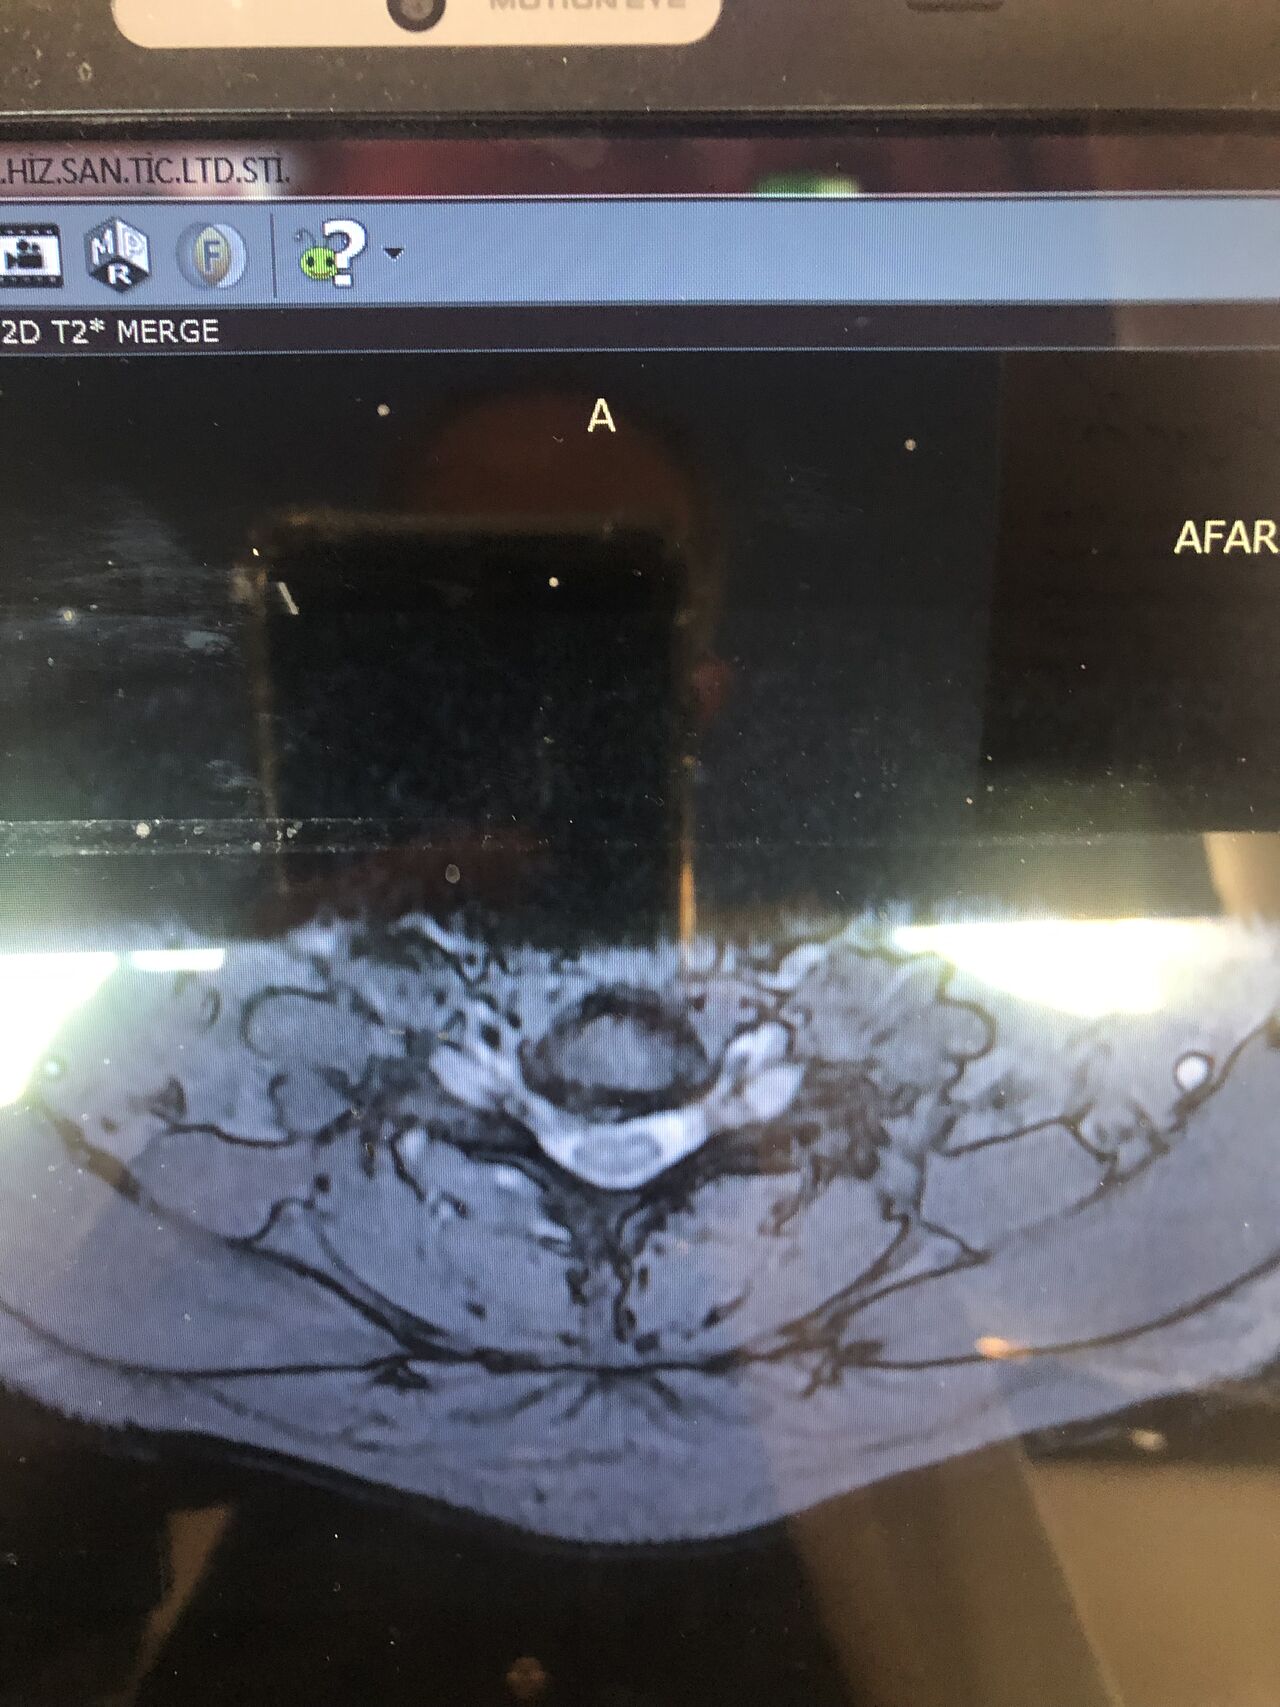

40 yrs old male patient presented to my office who had severe R gluteal pain and radicular pain along R L5-S1 now pain has reduced by 80% in his motor exam had R big toe L5 motor reduced to 4+\5 and R S1 DTR was 0 while L S1DTR was 1+

We did EMG/NCV which showed Mod- sever R L5 S1 irritation without any active axonal loss

I had to decide to refer him for surgery or not patient didn’t have any treatment meanwhile

I ordered new L/S mri

I posted his new mri and old mr

Which was 20 days ago and have posted all below

The first 12 mris had been done 20 days ago

After those first 12 MRIs i have posted new MRIs which were done yesterday

After seeing his new mri and emg/ncv and getting sure his neurological deficit is not active and progressing i told patient he doesn’t need surgery at this time and released him with some advices and exercises